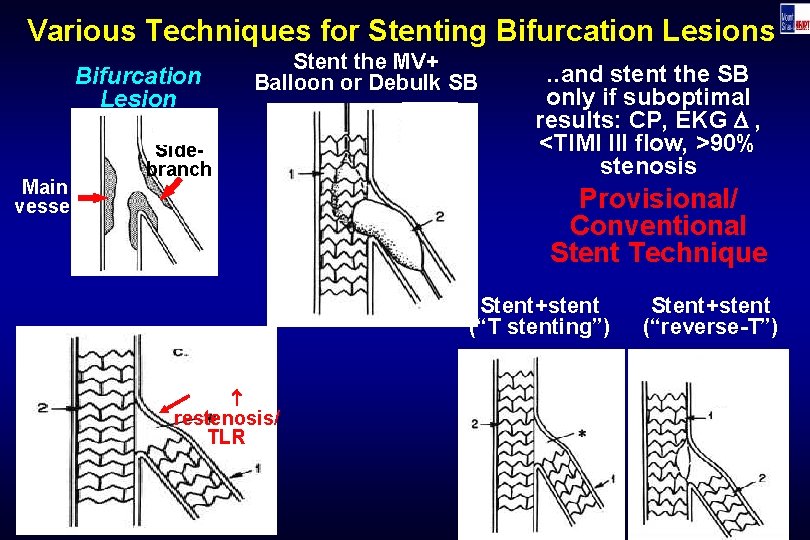

Various Techniques for Stenting Bifurcation Lesions Stent the MV+ Balloon or Debulk SB Bifurcation Lesion Main vessel Sidebranch . . and stent the SB only if suboptimal results: CP, EKG , <TIMI III flow, >90% stenosis Provisional/ Conventional Stent Technique Stent+stent (“T stenting”) restenosis/ TLR Stent+stent (“reverse-T”)